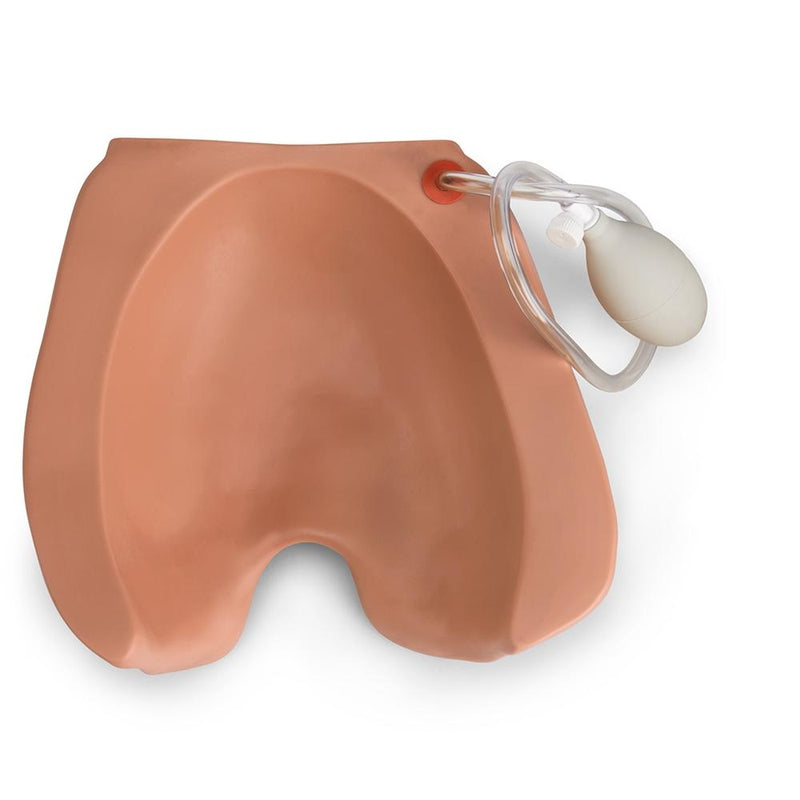

The Leopold's Maneuvers and Palpation Abdomen for Obstetric Susie® is a one-piece fetal baby with palpable fontanelles, spine, shoulders, elbows, and knees useful for labor and delivery skills training. The fetal baby may be used with Gaumard's Obstetric Susie® S500 simulator in normal, breech, or transverse position. Elevation cushions lift the fetal baby so participants can go hands-on and practice Leopold maneuvers and external version exercises.Palpation Module for Leopold Maneuvers S500.3

- One piece fetal baby with palpable fontanelles, spine, shoulders, elbows, and knees

- Fetal baby may be placed in normal, breech, or transverse position

- Fetal baby cradled between two “cushions”

- Cushions may be inflated independently of the other; inflation of the lower cushion raises the fetus to desired posi tion; inflation of the upper cushion creates a firm abdomen as in the ninth month of pregnancy

- Fetal baby

- Upper and lower cushions that cradle baby

- Inflation devices